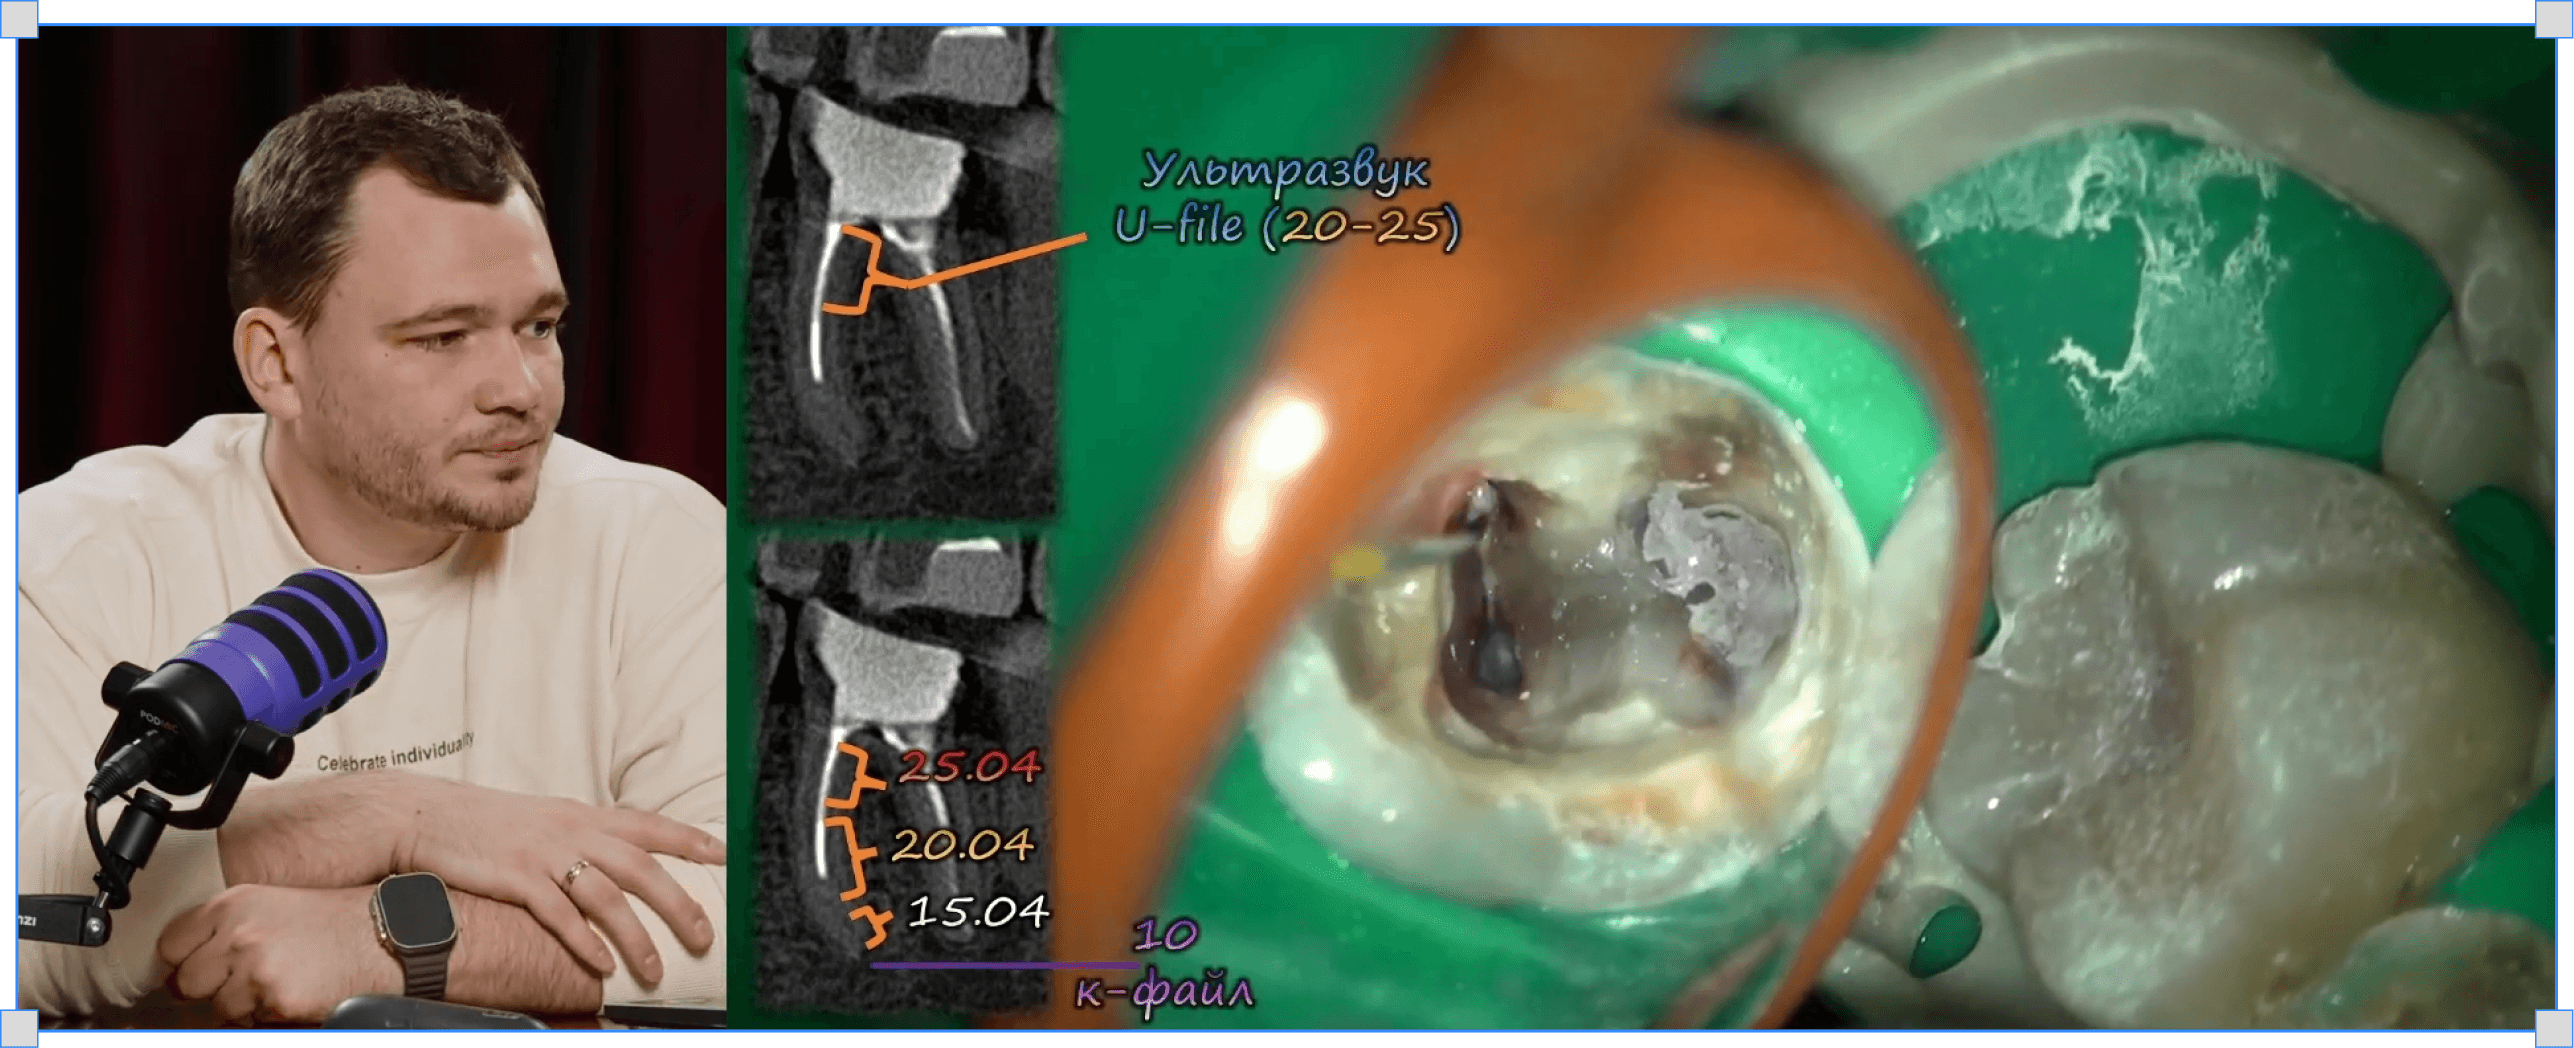

Розпломбування резорцин-формалінових зубів

Микола Сорухан

Розпломбування резорцину

Чіткі протоколи видалення резорцин-формаліну

Сходинки. Тактична карта обходу (MB-, ML-, DB-, DL-канали)

Продавлювання текучого сілера під гарячою гутаперчею